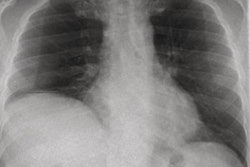

In one case, an 81-year-old woman with no history of asthma developed acute expiratory wheezing and hypoxemia after undergoing transcatheter aortic valve implantation for severe aortic stenosis. A portable chest x-ray showed mild cardiomegaly without overt pulmonary congestion or infiltrates.

Bedside DCR, however, as seen above, revealed increased lung translucency during inspiration, while postprocessing demonstrated reduced pixel-value fluctuations in both lungs, suggesting impaired ventilation and diffuse bronchospasm, the authors wrote. After bronchodilator therapy, the patient’s wheezing and oxygenation improved within one hour.

Based on the clinical course and therapeutic response, the episode was diagnosed as an acute asthma exacerbation, the authors noted.

“Follow-up DCR confirmed recovery of ventilation in both lungs,” they added.